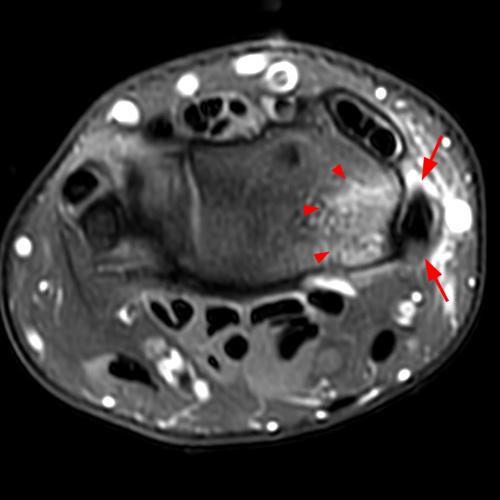

Clinical History: A 68-year-old female presents with radial-sided pain and swelling. Axial T1-weighted (1A), axial fat-suppressed proton density-weighted (1B), and coronal fat-suppressed proton density-weighted (1C) images are provided. What are the findings? What is your diagnosis?

Figure 2: The axial T1-weighted (2A), axial fat-suppressed proton density-weighted (2B), and coronal fat-suppressed proton density-weighted (2C) images demonstrate a thickened extensor retinaculum, surrounding soft tissue edema, and fluid signal in the first extensor compartment of the wrist (arrowheads). Marrow edema is noted within the subjacent radius (asterisks). A single extensor pollicis brevis and two abductor pollicis longus tendon slips are present with heterogeneous intrinsic signal.